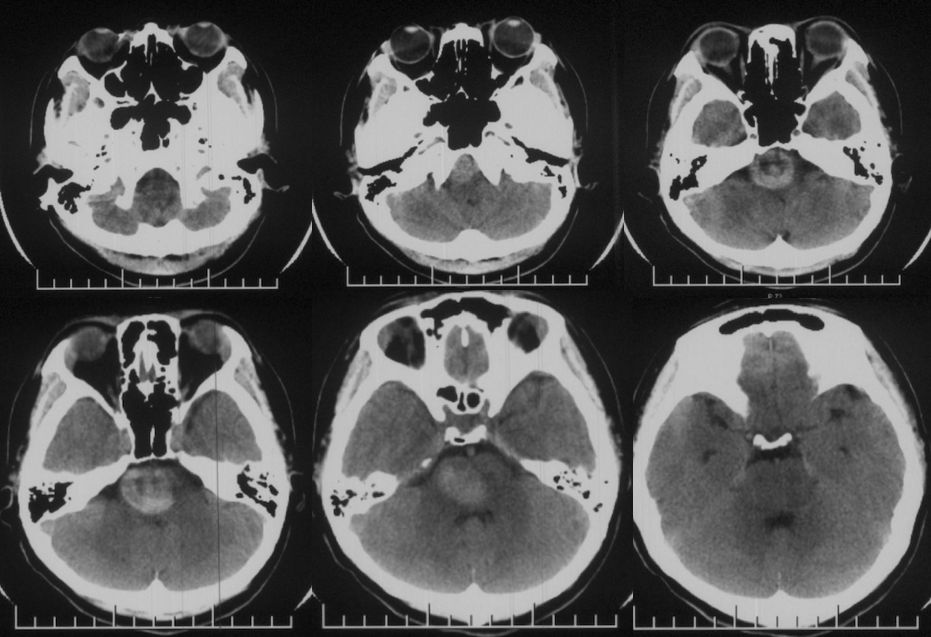

当地医院头CT:右侧脑干占位(2019-09-06)(图1)。

图1